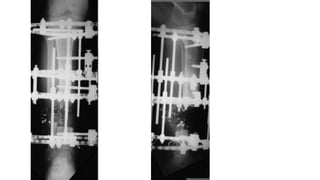

Ilizarov method • Lawof tension stress and distraction osteogenesis • Corticotomy is done in the fracture fragments and both the fragments are distracted. • When the desired length is achieved, distraction is stopped and consolidation of the new bone formed occurs • Gold standard in infective gap non union • Fibular osteotomy

• 21.

• Removal offixator: Atleast three cortices should be ossified in AP and Lat view xrays Protected weight bearing • Advantages: no skin incision is made, minimally invasive (wires and pins) Very little soft tissue handling Can correct length and deformities in three dimensions Patient can weight bear early after application

• 22.

• Disadvantages: Pin tractinfective Cumbersome for patient Requires sufficient physiotherapy post operatively Soft tissue contracture Kinking and stretching of neurovascular structures